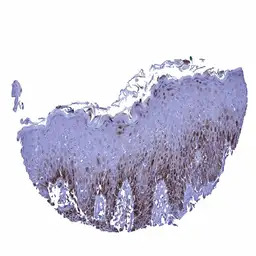

IHC-P analysis of human skin squamous epithelium tissue section using GTX04471 Glutamine synthetase antibody [MSVA-750M] HistoMAX.

In the skin, a nuclear and cytoplasmic Glutamine Synthetase staining can be seen in the lower third and in the top layers of the squamous epithelium.